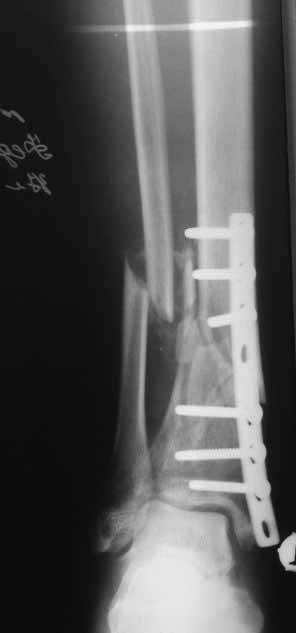

Спасибо за сообщения! Но мне видится что концы отломков большеберцовой кости мертвые. И поэтому мне представляется сомнительным что на гвозде даже с обработкой зоны ложного сустава и костной пластикой что-нибудь срастется. Может я и не прав, но по моему без резекции концов сантиметра на 4 перелом не срастется. Но, опять же, жду советов.

Да уж! Ни один из 3-х оперативных методов предшествующего лечения не был исполнен правильно. Везде был серьезный брак. Хотя любой из методов вполне мог бы и должен был бы привести к сращению,...если бы, да кабы.. В результате имеем то, что имеем. Что делать? Во-первых - подумать. Во-вторых - еще раз подумать. В третьих - еще больше подумать.

Иван, Вам видится зона перелома мертвой, а мне вовсе нет. Есть ли возможность сделать сцинтиграфию с технецием? Это может доказать нежизнеспособность или воспаление концов. Тогда есть резон для такой "крайней" меры как резекция. Есть ли клинические признаки инфекции в области первичной раны?, п\операционных рубцов?, в местах проведения спиц (нет ли спицевого остеомиелита)?.. В общем, вопросов может быть много.

Если нет данных за инфекцию в зоне перелома мы бы аппараптом дозированно устранили деформацию и, не удаляя дистальный фрагмент сломанного гвоздя, закрыто, после рассверливания заштифтовали бы достаточно толстым и надлежащей длины гвоздем.... Если есть спицевой остеомиелит, то также сначала аппарат, затем рассверливанме и цементный спейсор с а\б согласно посевам, через 2-3 недели удалить спейсор, повторно рассверлить и заштифтовать штифтом, возможно покрытым антибиотиком. А если Вы умело владеете техникой Илизарова, и больной согласен, можете оставить аппарат как окончательный метод фиксации....

В любом случае, если нет инфекции в зоне несращения и кость жизнеспособна, упаси Вас Бог что либо открывать и добавлять свободную костную пластику. Надо попытаться все сделать закрыто. Если откроете, то через пару месяцев, а может и раньше, все закончится резекцией и значительно большей чем 4 см...

Если там инфекция, что не исключено, судя по представленным данным, то вариантов нет - резекция в пределах здоровой кости.